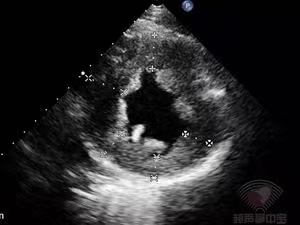

术后复查超声心动图